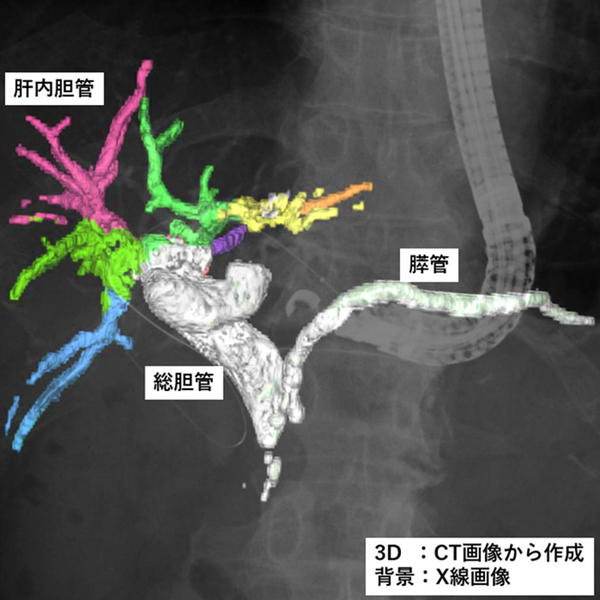

また,今回発売する二つのモデルは,2025年4月に発売したソフトウェア「VisualAID-ERCPプランニング-」*7にも対応。本ソフトウェアは,ERCP中にCUREVISTAシリーズで撮影したX線透視画像上に3Dで作成した胆管・膵管の画像を重ねて表示することで,臓器との重なりなど解剖学的構造の把握が容易になることが期待できる。本ソフトウェアでは,これまでCT画像とMRCP画像*8で3D画像を作成する必要があったが,今回新たにCT画像のみで3D画像を作成できるようになった。これにより,MRI撮影を実施しない医療機関での対象被検者の増加が見込まれる。さらに3D画像作成時にCT画像とMRCP画像の位置合わせの作業が不要となることでワークフローの向上が期待できる。同社のIT技術とX線透視装置を連携させた新しいワークフローにより,医師の診療の高度化・効率化に貢献する。

ERCP中に撮影したX線透視画像上にCT画像を用いて作成した胆管・膵管3D像を重畳表示している様子